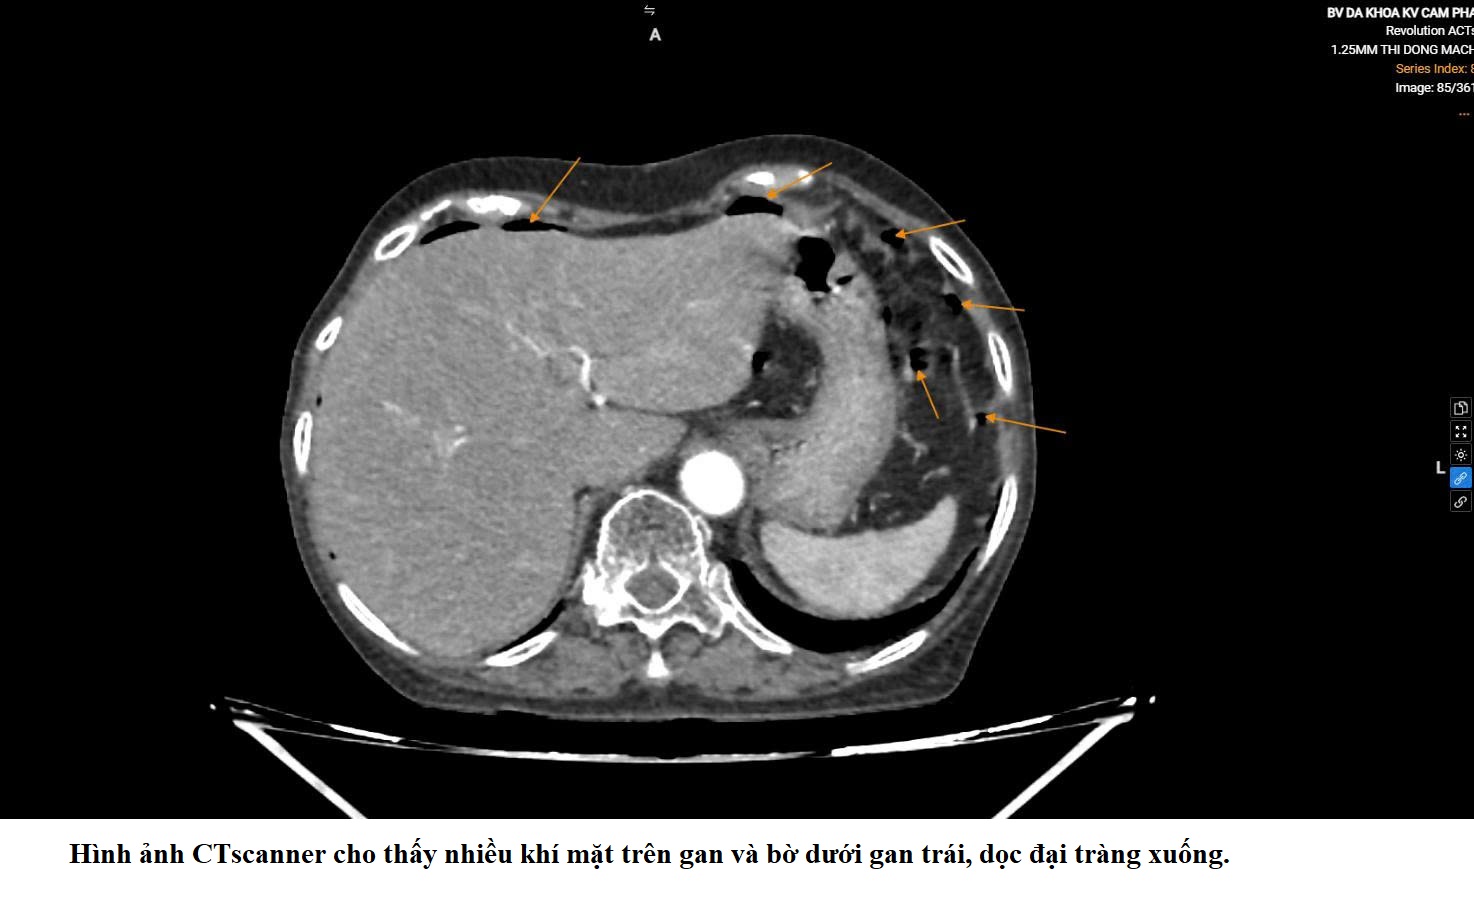

GIÀNH LẠI SỰ SỐNG TỪ CA THỦNG ĐẠI TRÀNG HIẾM GẶP: DẤU ẤN PHỐI HỢP LIÊN CHUYÊN KHOA TẠI BỆNH VIỆN ĐKKV CẨM PHẢ

(Cập nhật: Lúc 15:05, Ngày 10 tháng 04 năm 2026)